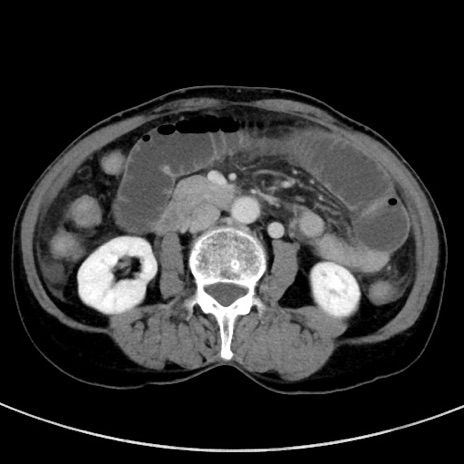

症例23(横断像)

【症例】70歳代女性

【主訴】下腹部痛・嘔吐

【現病歴】2日前より腹痛あり。昨日嘔吐あり。症状改善しないため来院。

【既往歴】胃GISTに対して胃部分切除後。

【身体所見】BT 37.1℃、BP 128/77mmHg、腹部:平坦・軟、下腹部に圧痛あり。

【データ】WBC 10200、CRP 0.31